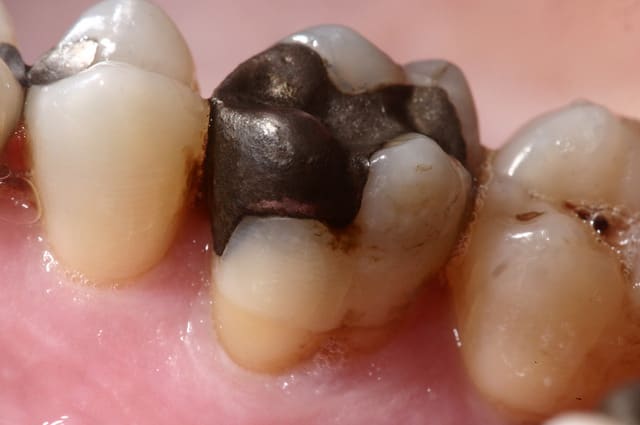

c'est un Hg sur moi;)

et c'est bien Brouillet qui l'a fait à la fac:

une seance de 2 heurs pour le faire ( ya un petit pins dentinaire au niveau de la face MP manquante ) + une demi heure de polissage la semaine suivante.

le polissage a mal resisté aux 30 ans ;) ça ressemblait a l'armure d'arthur aprs qu'il ait trouvé Excalibur tellement ça brillait. c'etait avec un des tout premier non gamma 2 qui en fait, n'etaient pas encore comercialisés je crois.

bon je t'aide, ils ont 20ans et j'ai pas repoli pour la photo (du reste déjà postées il y a un bail)

24ans après verif dossier

dents vivantes, pas de tenon dentinaire par contre (je suppose qu'entre les 6ans qui séparent les deux cas on avait décidé que c'était iatrogène)

sauf que j'ai les 2 cotés de la photos;) qd ça lachera c'est sur 2 mm en haut de la cuspide qu'il faudra de tout e façon recouvrir .

b/ la felure est là au moins depuis 2006 et n'a pas bougé.